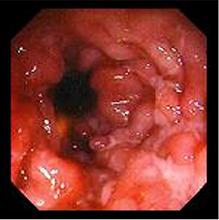

Lesion ulcereux : stade

evolutive |

Forme grave : lesion

ulcero-proliferatif nodulaire |